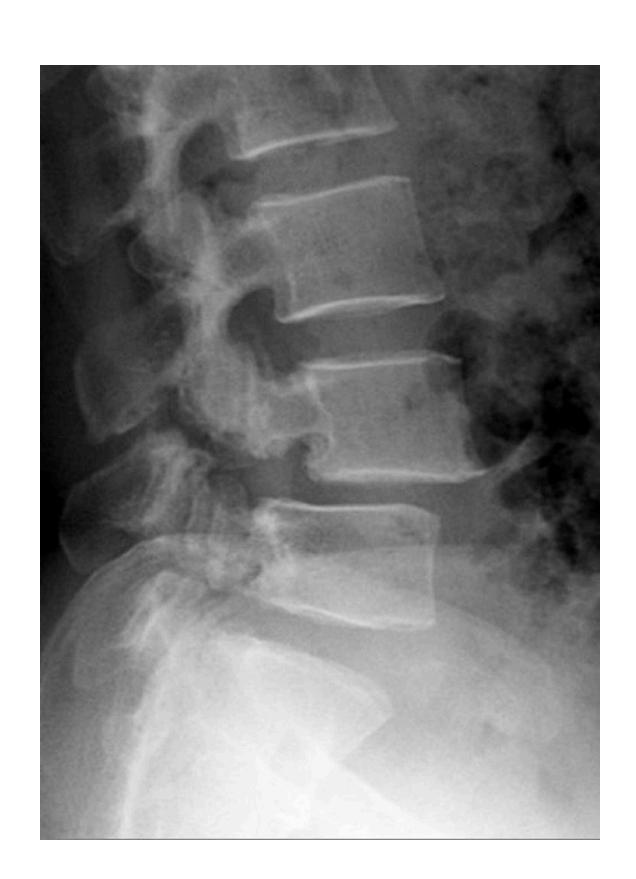

Spondylolisthesis

Findings? X-ray of cervical spine should include all C vertebrae and T1. Anterior slippage of C4 over C5 and pars-interarticularis fracture (decapitated scotty dog)

Diagnosis? Pars interarticularis fracture (decapitated scotty dog)

Anterior displacement of L4 over L5, pars interarticularis disruption, osteopenia

Nerve compression may cause inability to control bowel and bladder sphincter, chronic pain and numbness